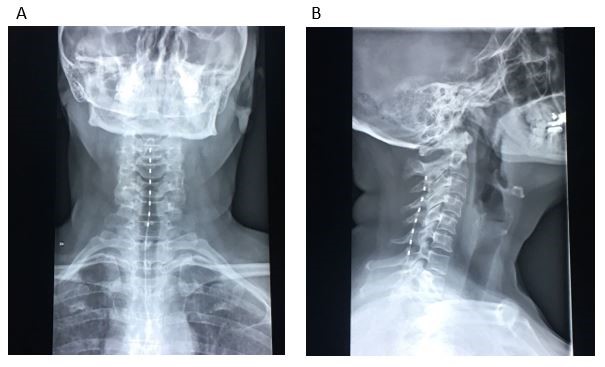

A Novel Approach with Spinal Cord Stimulation for the Treatment of Chronic Pain in Eagle’s Syndrome: A Case Report